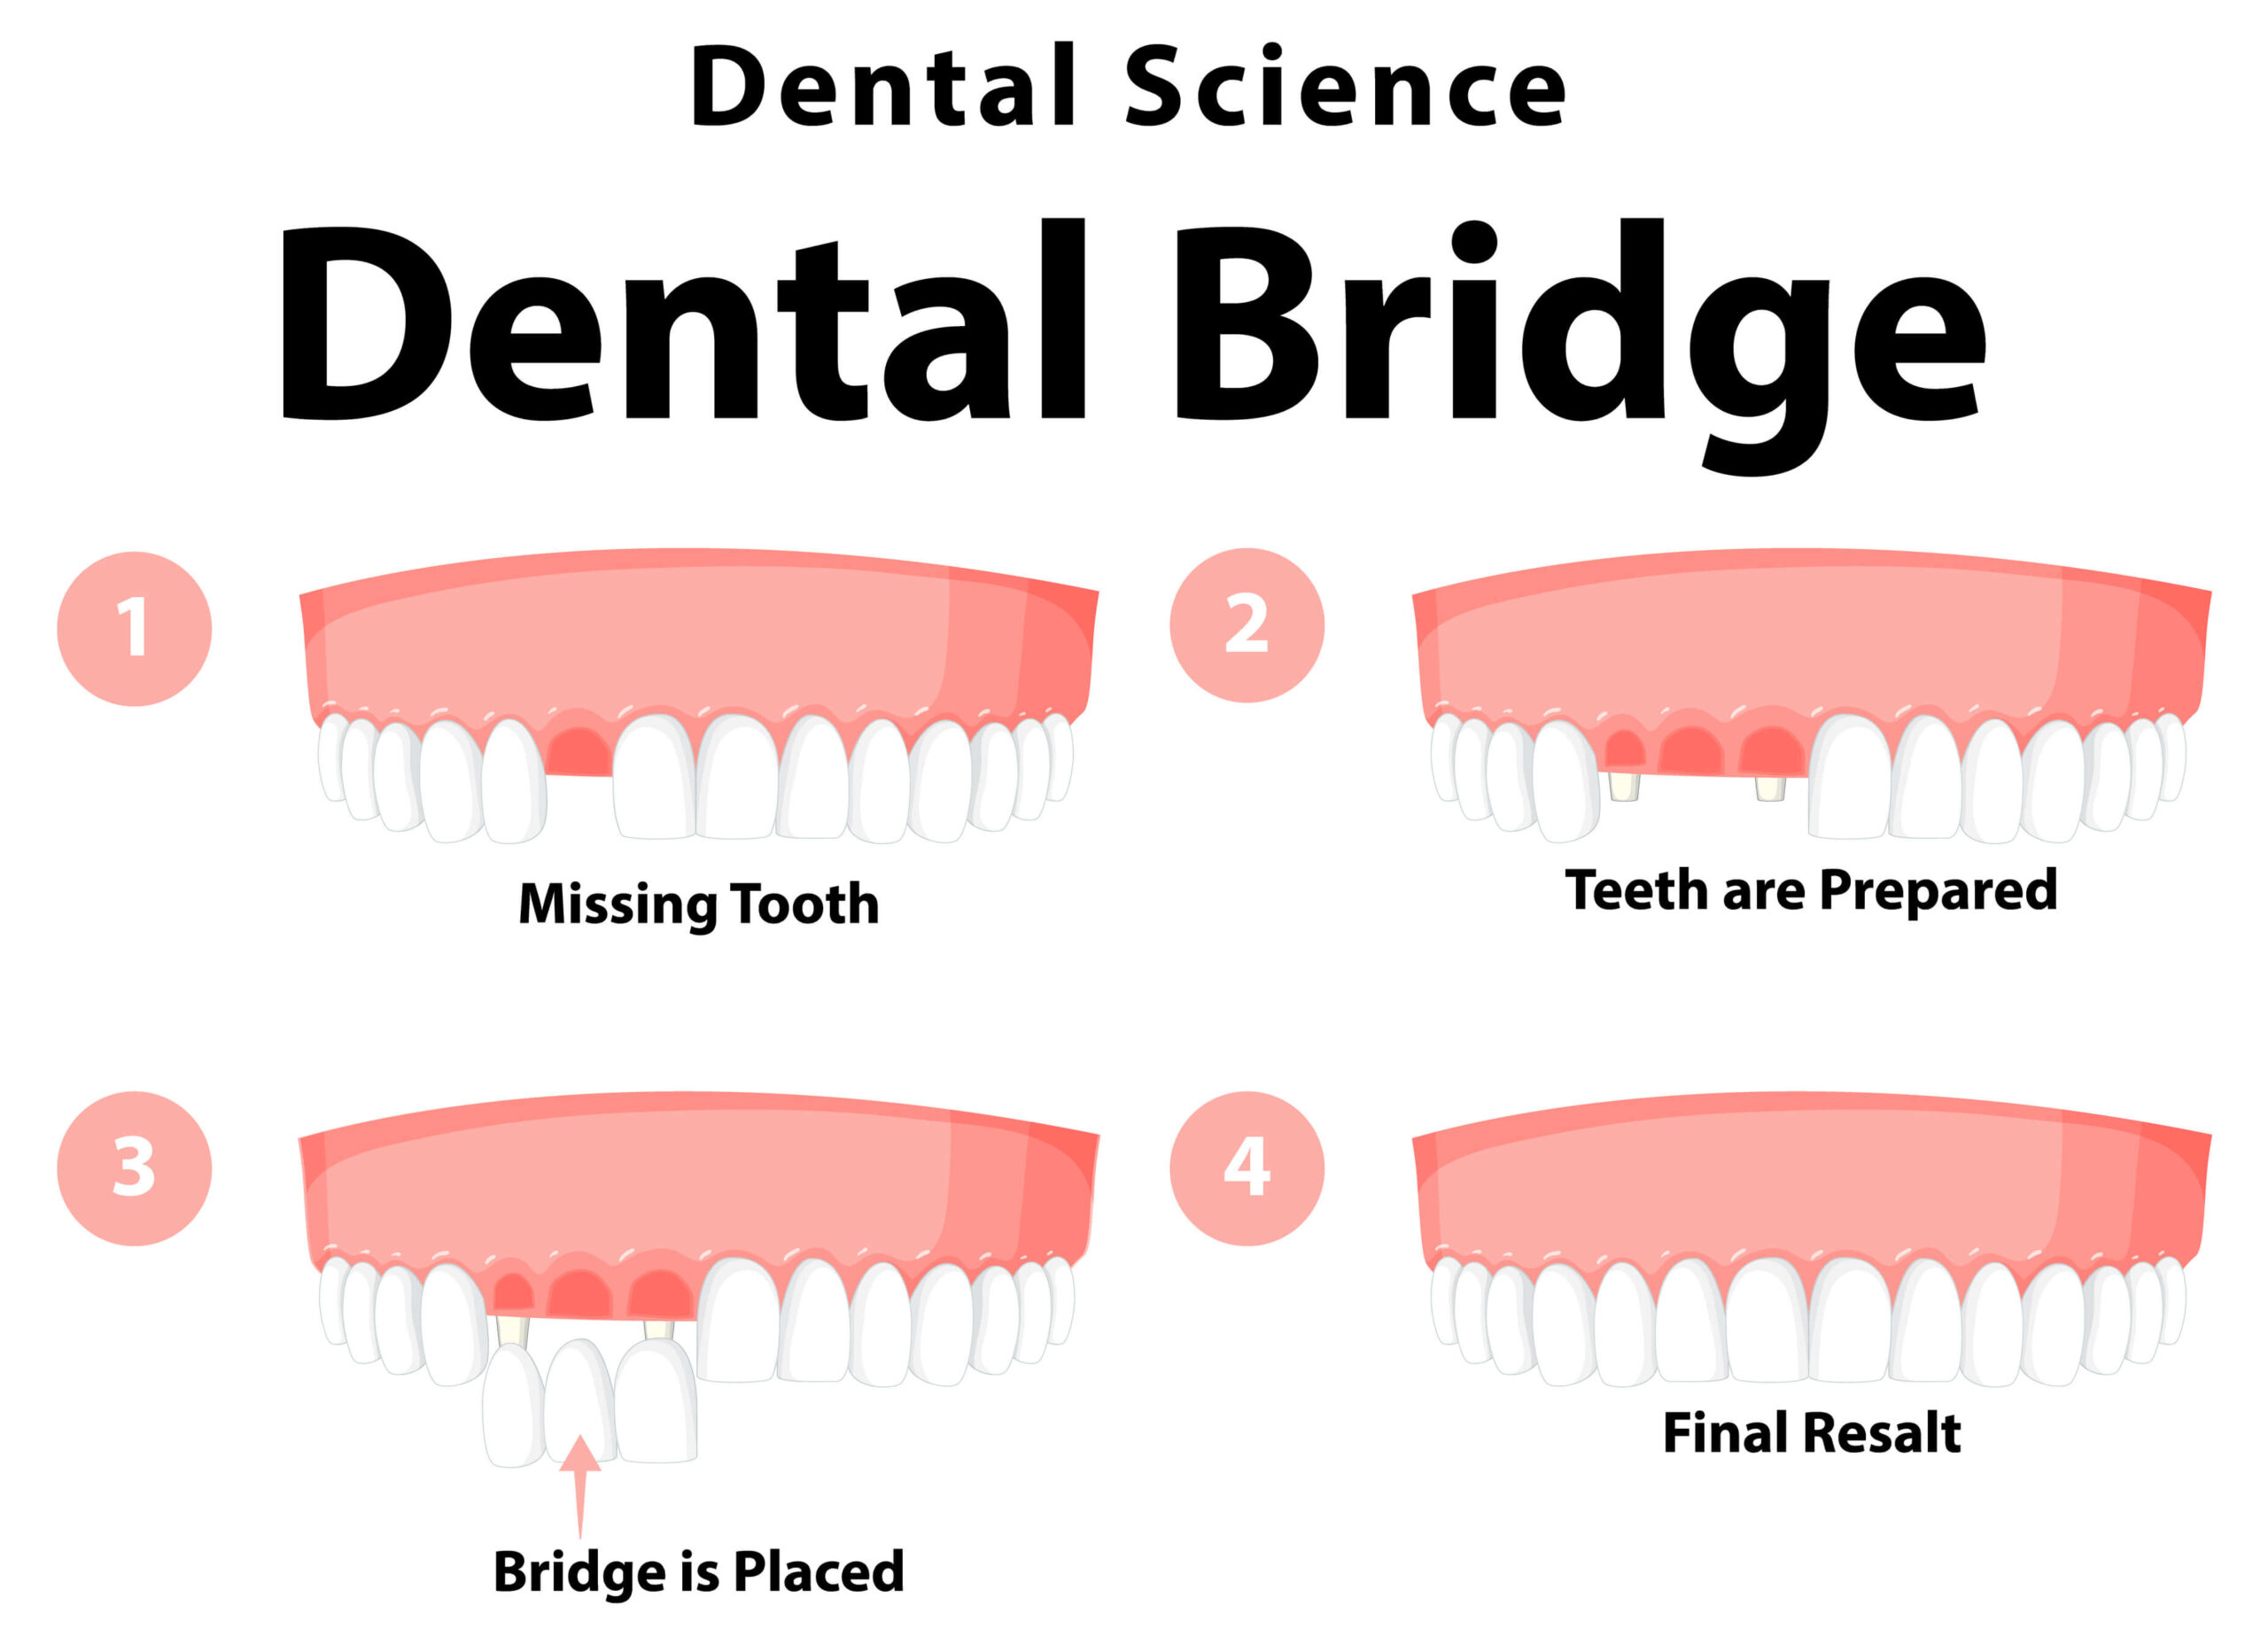

Understanding Dental Bridges

Why Choose Dental Bridges Treatment?

Our Approach to Dental Bridges Treatment